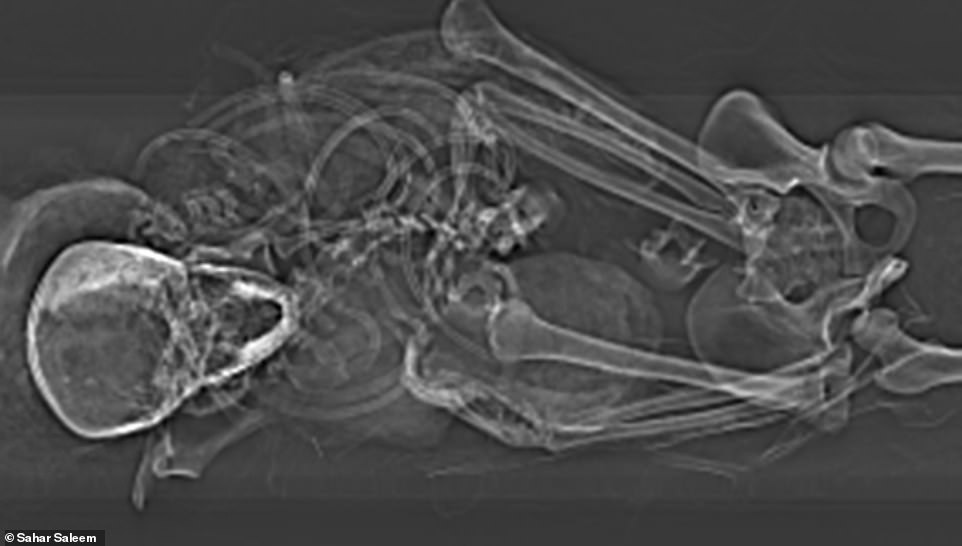

Thông qua phương pháp chụp cắt lớp vi tính (chụp CT) xác ướp, giới chuyên gia phát hiện ông hoàng này có cái chết thảm khốc và đau đớn.

Hai tay của pharaoh Seqenenre Taa II không có vết thương nào và ở trong trạng thái nắm chặt. Từ đây, các chuyên gia suy đoán ông bị trói chặt 2 tay khi bị kẻ thù sát hại.